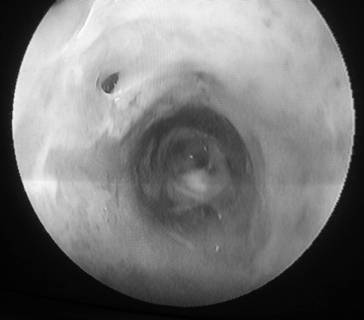

После восстановления листков париетальной брюшины на месте иссечения клетчатки в пристеночных отделах образуется свободное пространство в виде замкнутой полости, в которой может скапливаться периферическая и промежуточная лимфа. При длительном поступлении лимфы в полости оседает фибрин и образуется соединительная капсула, из которой формируется стенка лимфатической кисты. Окончательное формирование лимфатических кист происходило на 21–28 день после операции (рис. 2).

1

Рис. 2. Вид лимфатической кисты изнутри при лимфоцистоскопии.

1 – пересеченный во время операции Вертгейма коллекторный лимфатический сосуд в забрюшинном пространстве малого таза